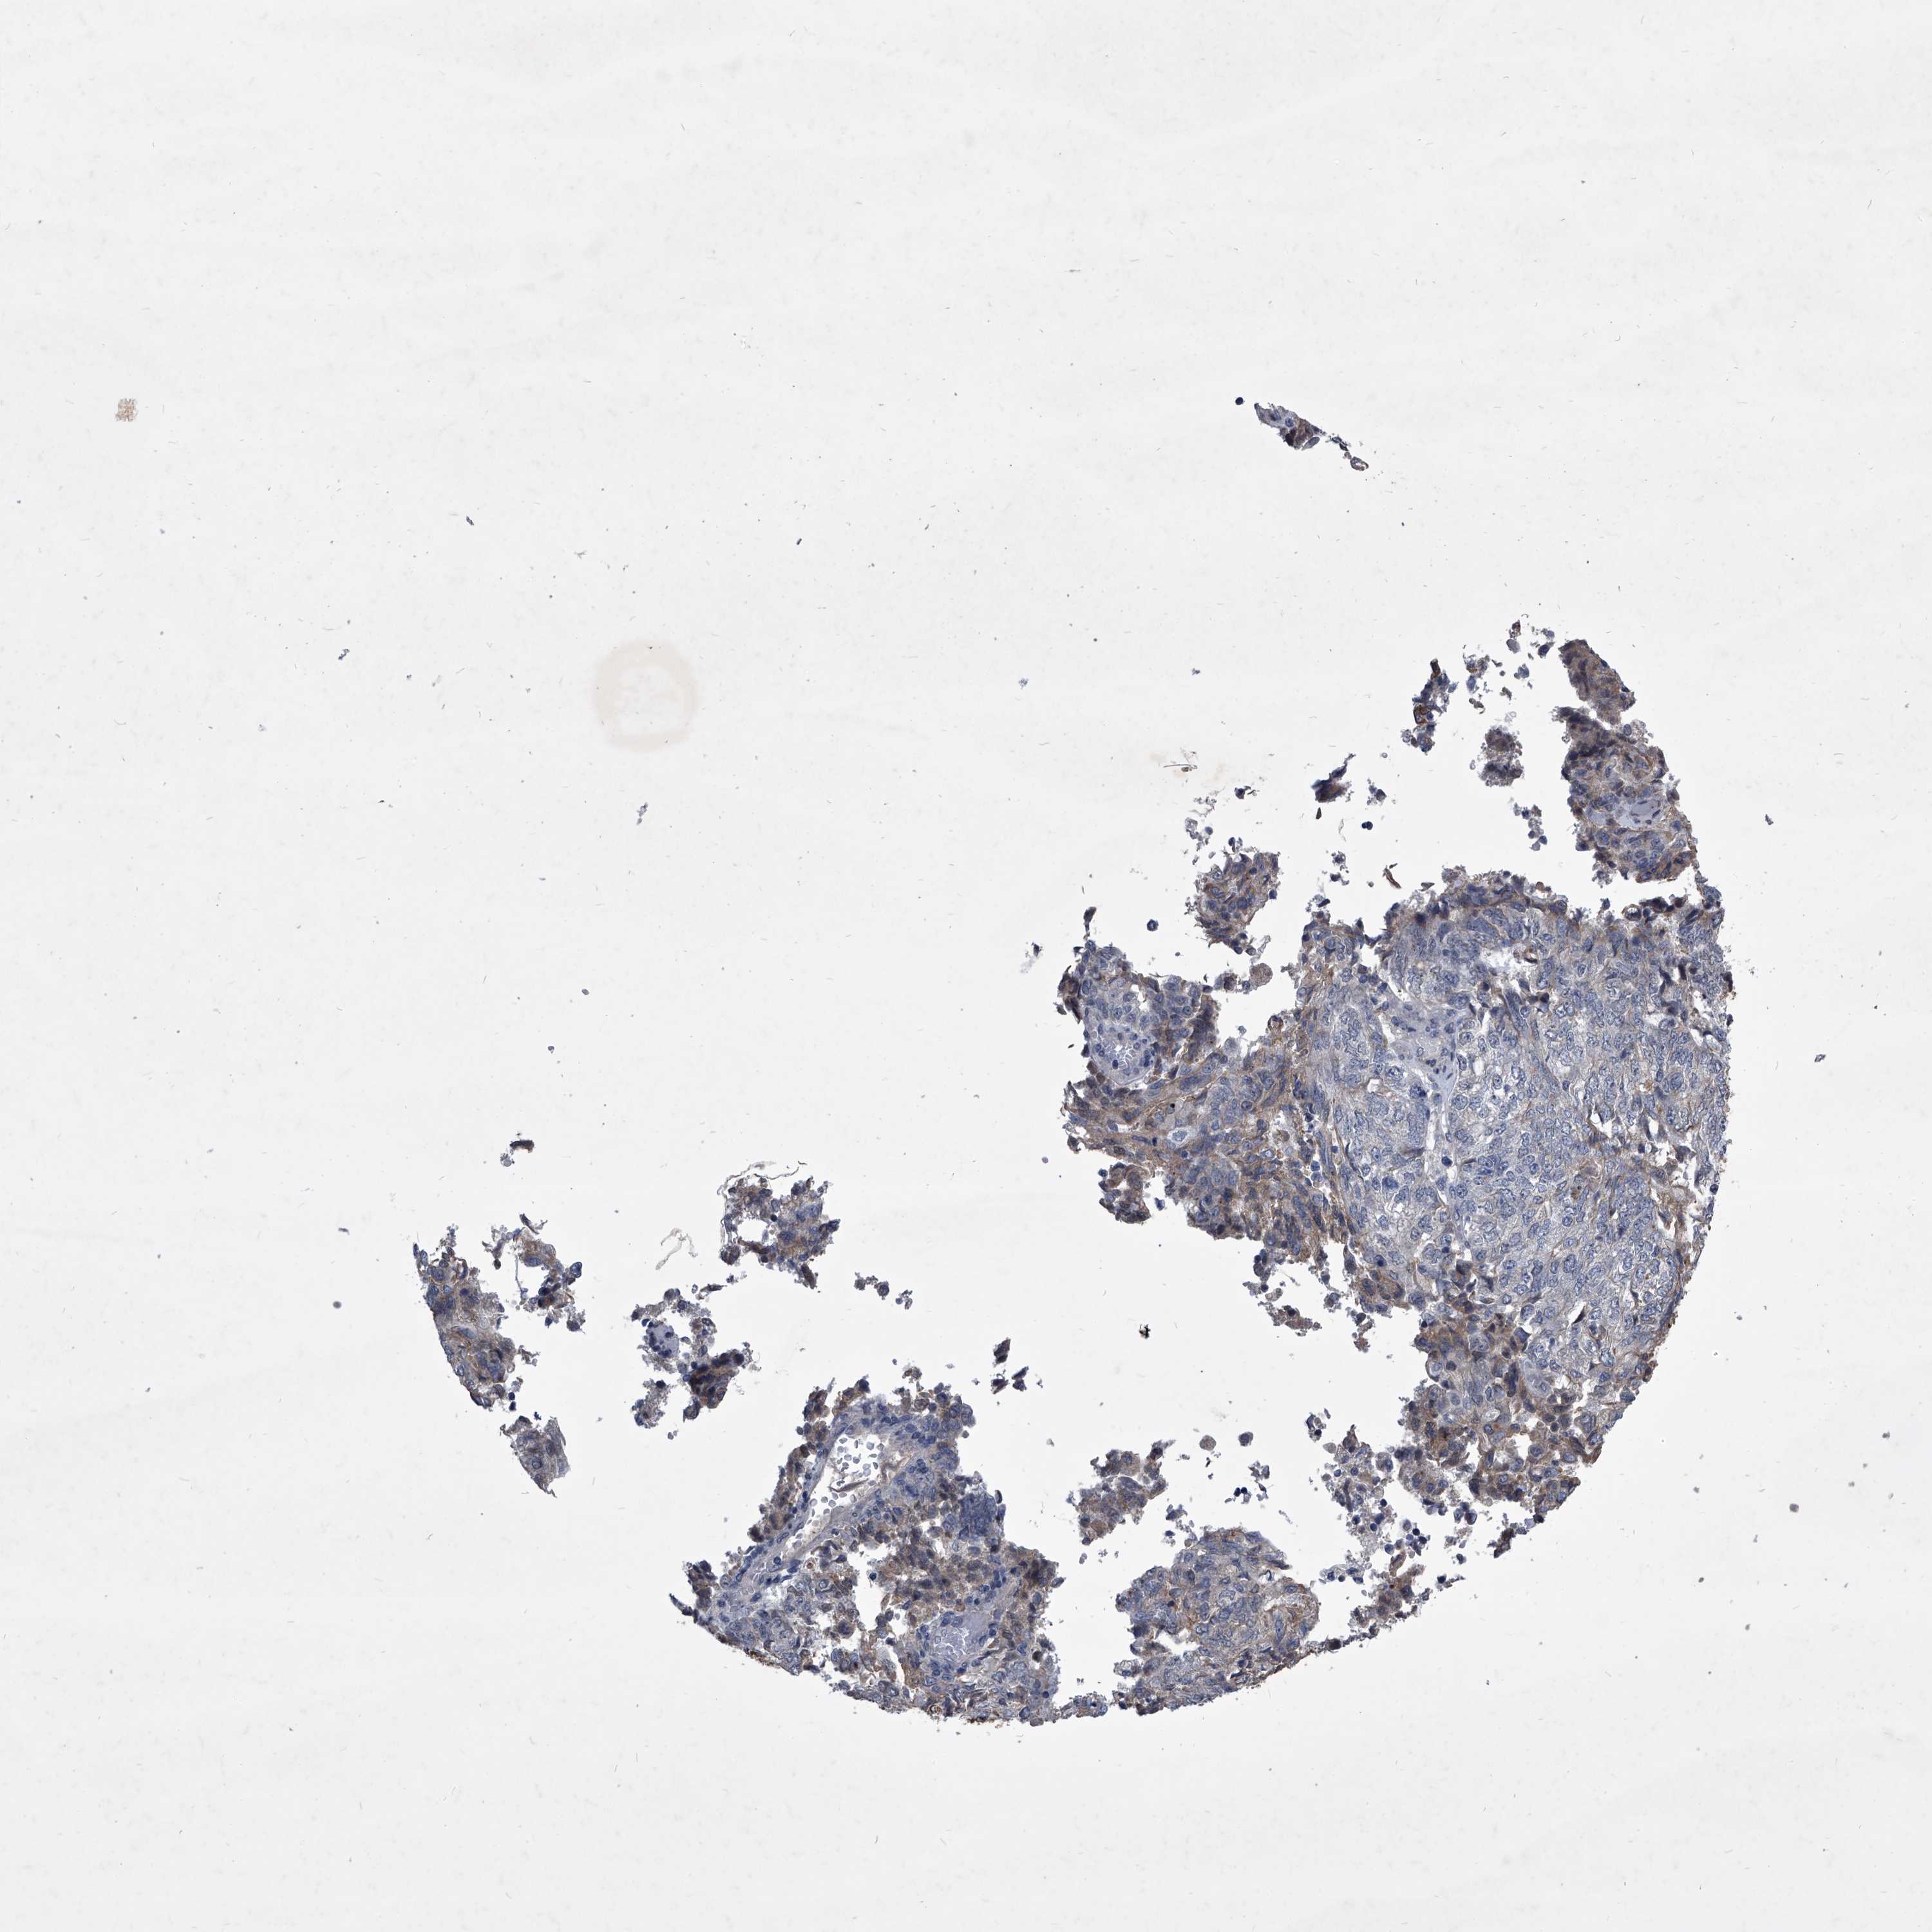

ENDOMETRIAL CANCER - Protein expressioni

A mouse-over function shows sample information and annotation data. Click on an image to view it in a full screen mode. Samples can be filtered based on level of antibody staining by selecting one or several of the following categories: high, medium, low and not detected. The assay and annotation is described here.

Note that samples used for immunohistochemistry by the Human Protein Atlas do not correspond to samples in the TCGA dataset.

Antibody stainingi

Antibody staining in the annotated cell types in the current human tissue is reported as not detected, low, medium, or high, based on conventional immunohistochemistry profiling in selected tissues. This score is based on the combination of the staining intensity and fraction of stained cells.

Each image is clickable and will lead to virtual microscopy that enables deeper exploration of all samples and also displays staining intensity scores, fraction scores and subcellular localization as well as patient and tissue information for each sample.

Antibody HPA030090

Antibody HPA030091

Staining

High

Medium

Low

Not detected

Intensity

Strong

Moderate

Weak

Negative

Quantity

>75%

75%-25%

<25%

None

Location

Nuclear

Cytoplasmic/membranous

Cytoplasmic/membranous,nuclear

Adenocarcinoma, NOS

Adenocarcinoma, metastatic, NOS